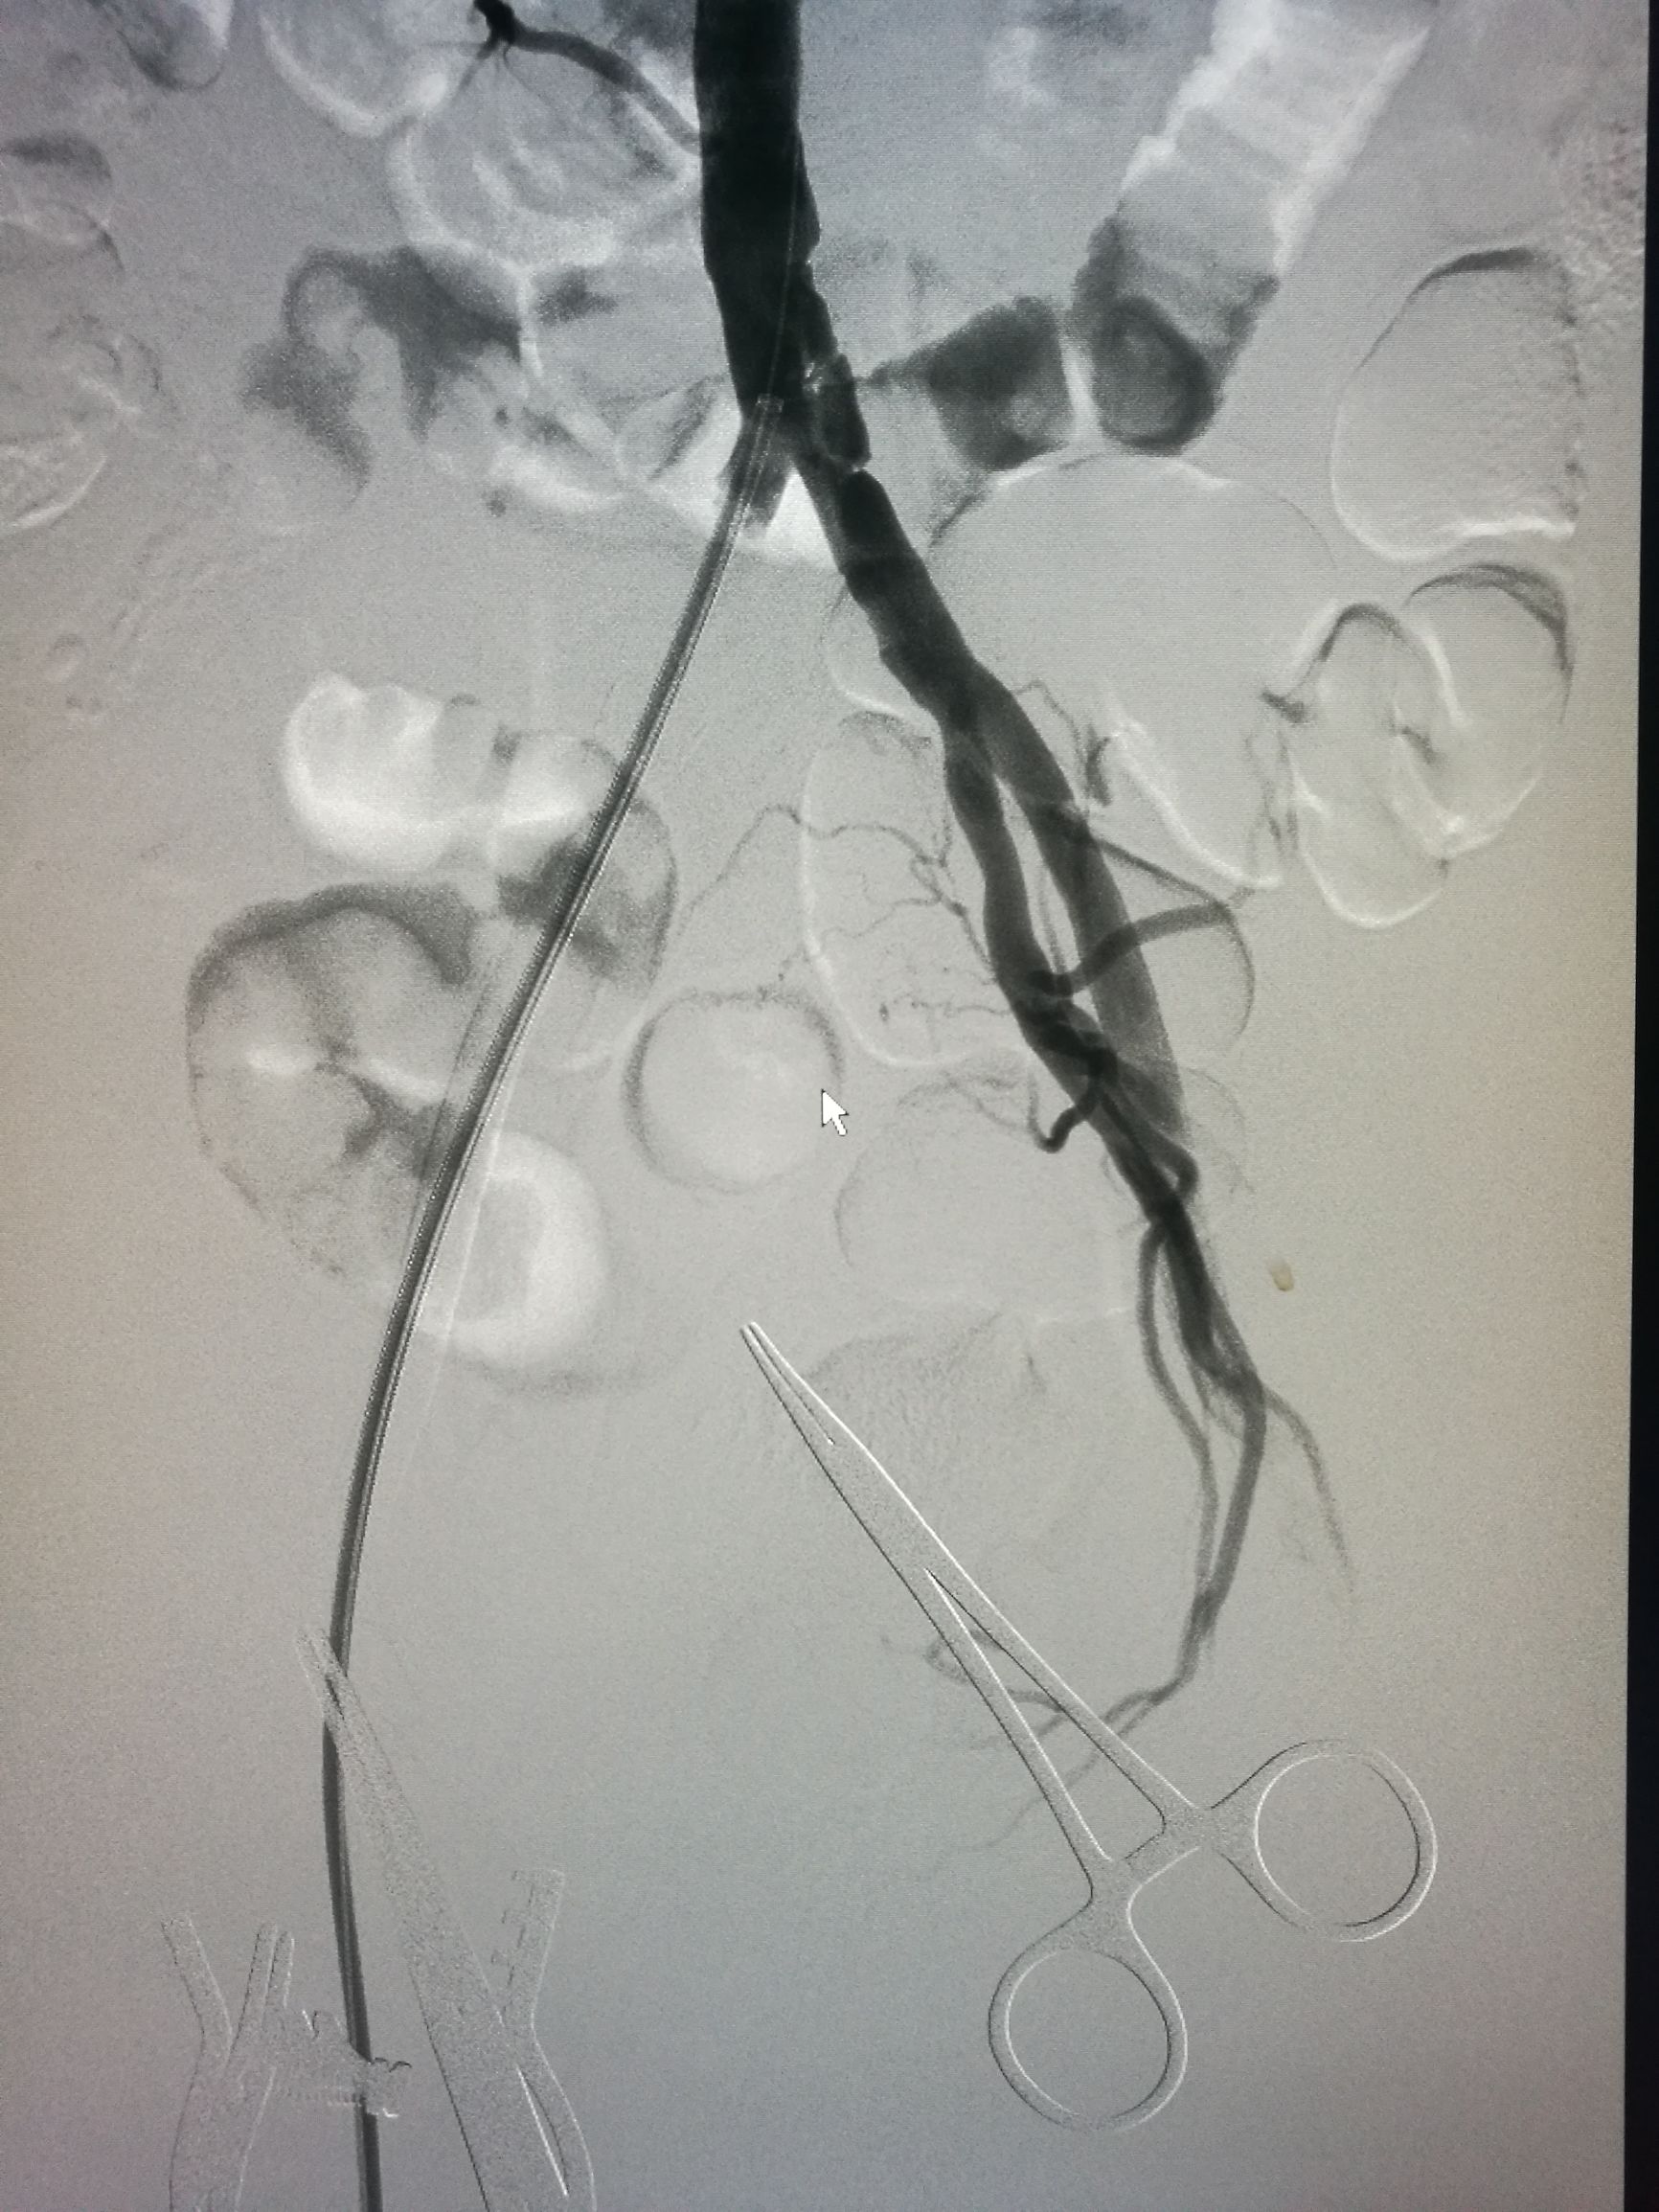

患者平卧位,常规消毒铺单,局麻下切开显露右侧股总动脉和股深动脉、股浅动脉。全身肝素化后,切开股动脉,对股浅动脉取栓后远侧回血好,对股深动脉反复取栓后出现汹涌回血。近端取栓后用导丝导管通过闭塞段到达腹主动脉下段,造影证实在真腔,用5*80mm球囊扩张后造影,髂动脉内有部分充盈缺损。植入巴德Fluency8*100和8*60覆膜支架后用7*60球囊扩张,造影管腔光滑(如图)。缝合动脉切口,关闭伤口,术毕。